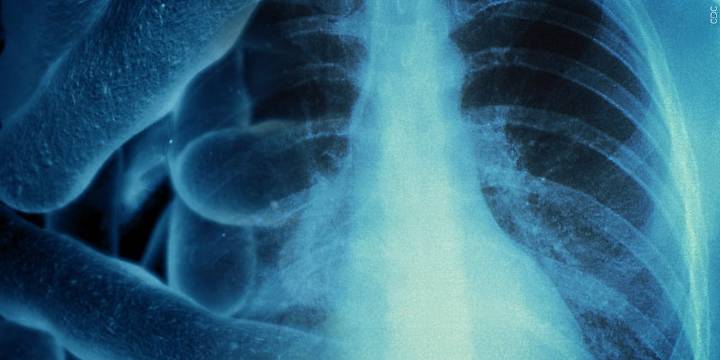

The Iowa Department of Health and Human Services first reported on the illness in the region on September 4. The disease sickened 74 people and killed two.

A specific bacteria causes Legionnaires’ disease and can grow in water systems, like large air conditioners.

Linn County Public Health officials said places with stagnant water like hot tubs, humidifiers, or unused shower heads can transmit Legionnaires’ disease if not cleaned properly.